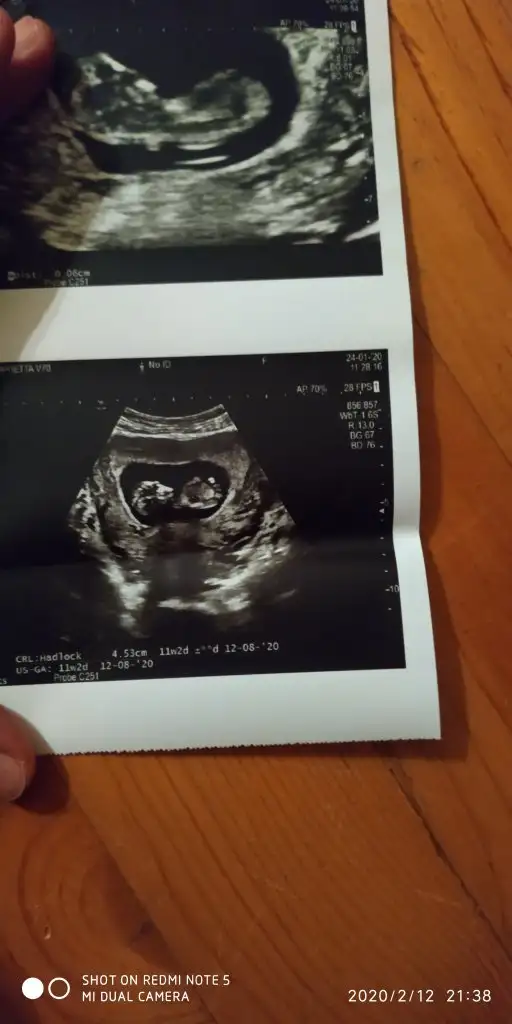

Ayin 18 randevum bende valla korkuyorum acikcasi gitmek istemiyor bir tarafim rabbim hayirlisini nasip etsin diye bol bol dua ediyorum

Canım bende merak ediyorum seni benimde 3 oglum var bu 4. Ins hayırlısıyla bi kızımız olur